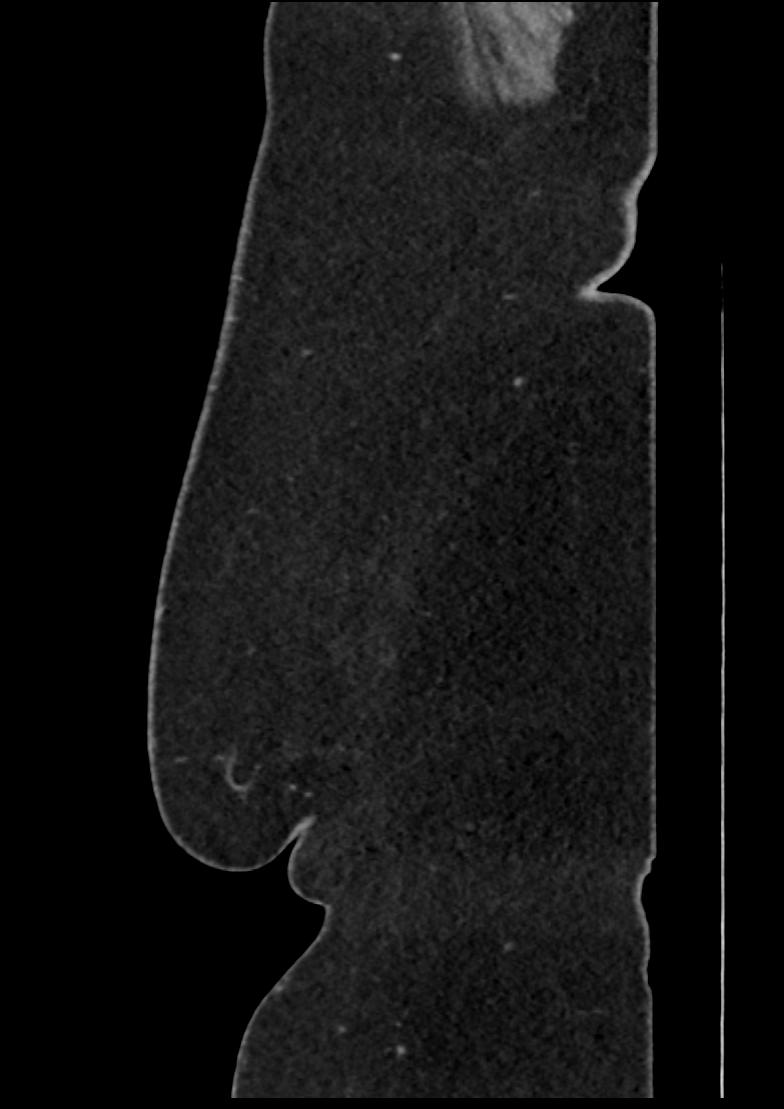

Patient: Padmakumar A. , *1988-04-24, PID: 3000069741773230809

Study Description: CT ABDOMEN

Image Series: Abdomen Sag 3mm [4]

<< Previous | Image 17 of 158 | Next >>